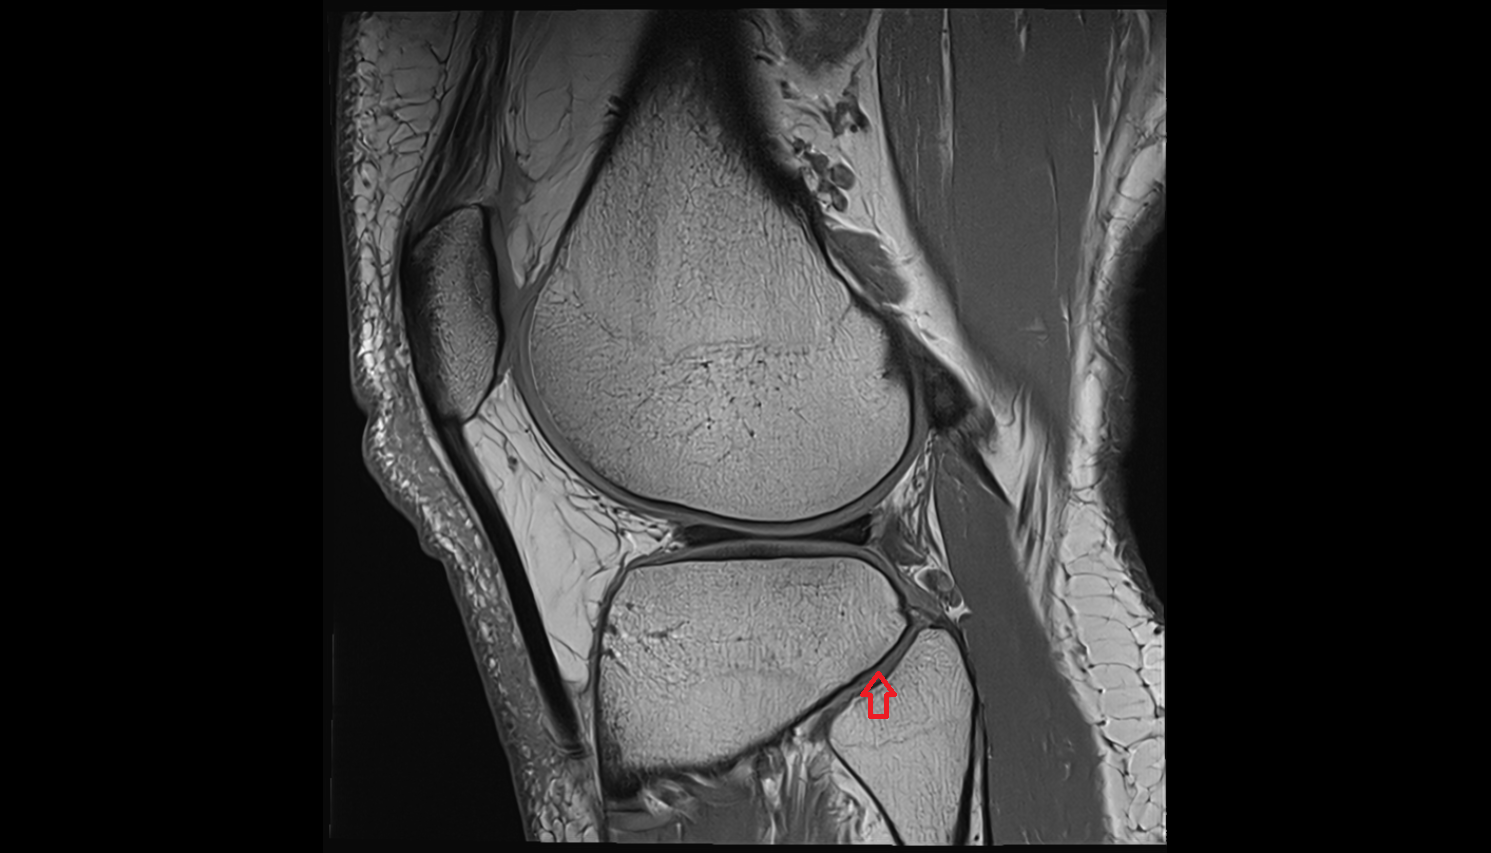

- Medial meniscus

- Lateral meniscus

- Anterior horn of medial meniscus

- Posterior horn of medial meniscus

- Body of medial meniscus

- Anterior root of medial meniscus

- Posterior root of medial meniscus

- Anterior horn of lateral meniscus

- Posterior horn of lateral meniscus

- Body of lateral meniscus

- Anterior root of lateral meniscus

- Posterior root of lateral meniscus